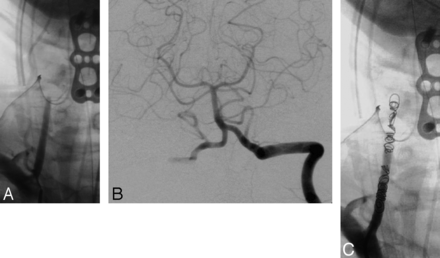

Asymptomatic occlusion of the cervical vertebral artery, particularly at the level of its origin from the subclavian artery, is not unusual in patients with severe atherosclerosis. In many such cases, segmental cervical collaterals effectively reconstitute the vertebral artery below the level of the skull base. These collateral vessels often arise from muscular branches of the vertebral artery, the ascending cervical branch of the thyrocervical trunk, or the deep cervical branch of the costocervical trunk (Fig 1). Furthermore, segmental spinal arteries and the normal confluence of both vertebral arteries provide a rich collateral supply to the posterior fossa.

A 24-year-old man with C6–C7 fracture dislocation, spinal cord injury, and traumatic occlusion of the left vertebral artery following a motor vehicle collision. DSA of the left costocervical trunk demonstrates distal reconstitution of the occluded midcervical left VA from the posterior deep cervical branch of the costocervical trunk. The left VA is occluded proximally.

A 35-year-old man with a C5 burst fracture, right vertebral artery occlusion, and spinal cord injury following a motor vehicle collision. A, Anteroposterior digital subtraction angiography of the right vertebral artery shows occlusion at the level of C5 before endovascular treatment. B, Anteroposterior DSA of the intracranial left vertebral artery demonstrates backfilling of the occluded right vertebral artery down to the level of the right posterior inferior cerebellar artery. C, Anteroposterior angiographic image demonstrates occlusion of the right vertebral artery stump secured with fibered coils to avoid emboli in spontaneous recanalization.

Dominance of the affected vertebral artery or the presence or size of the posterior communicating arteries did not affect the decision to perform the occlusion. In many cases, the dominant vertebral artery was already completely or near completely occluded, or the need for occlusion of the dominant vertebral artery was clinically imperative. In cases of complete occlusion of the vertebral artery secondary to traumatic injury, coil embolization of the occluded stump (Fig 2C) was performed to prevent emboli in case of spontaneous recanalization.